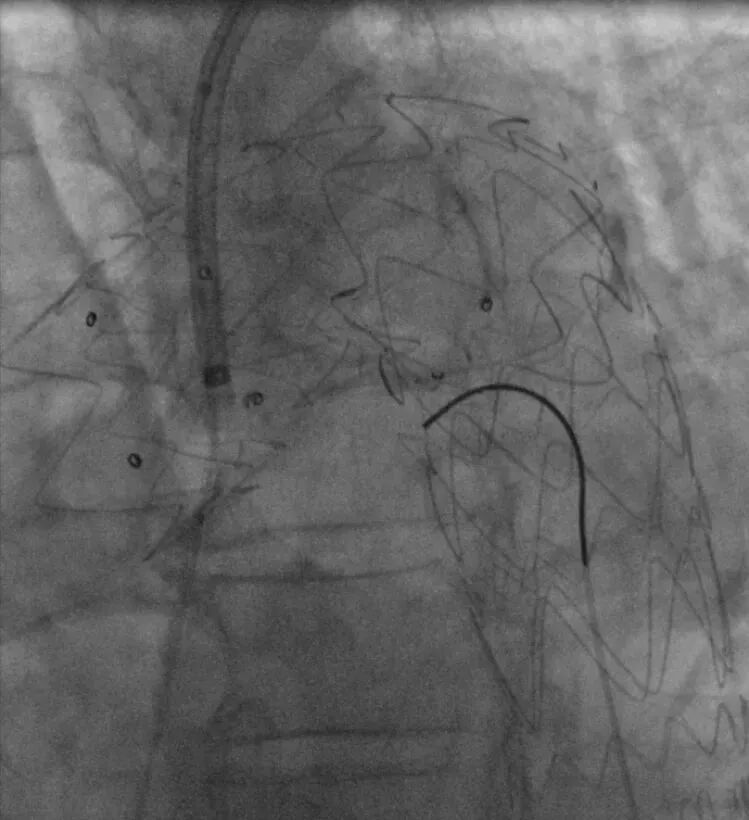

2. 术中精准测量左颈总动脉根部远端处主动脉直径,确定华脉泰科胸主动脉覆膜支架型号。右侧股动脉引入超硬导丝,退出金标猪尾导管,送入华脉胸主覆膜支架系统,精准定位于左颈总根部远端位置,释放2-3节,再次确认位置无误后,释放全部支架及后释放裸支架,再次造影示:支架位置精准、展开良好,未见成角畸形,左颈总动脉血供良好,无明显内漏。

置入华脉胸主支架

近端定位LCCA根部远端

缓慢释放2节再次确认位置

全部释放支架